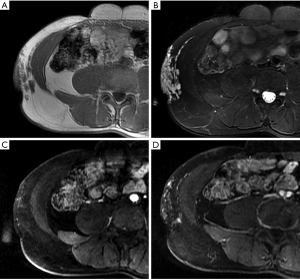

Liposarcomas

Liposarcomas are the second most common soft tissue sarcomas, accounting for 10–35% of all soft tissue sarcomas (13). Liposarcomas show the most striking diversity in pathological and biological behavior and can be categorized into several subtypes, including dedifferentiated, myxoid, pleomorphic, and mixed (23). The imaging findings of liposarcomas are frequently distinct. On CT and MRI, focal or diffuse areas of fat associated with nonlipomatous components are commonly detected, and the diagnosis can be easily determined in these cases. However, the diagnosis is not achievable in other cases without fatty tissue in the lesions (Figure 3). MRI is useful for distinguishing well-differentiated from poorly differentiated liposarcomas (11).

On CT, desmoid-type fibromatosis usually appears as a round or oval, nonspecific soft tissue mass with a density similar to that of muscle. Generally, it does not grow across the midline and is significantly enhanced after contrast injection. It shows low-to-intermediate signal intensity (SI) on T1WI and high SI on T2WI. Internal band-like findings of low signal heterogeneity on all sequences are relatively distinct on MRI (Figure 4). These low-SI bands are common (62–91% of cases) in desmoid-type fibromatosis compared with other neoplastic lesions and are related to the collagenized and hypocellular band regions observed on gross pathological examination, representing fibrous and collagenized regions (26,27). Extension along fascial planes (i.e., the “fascial tail” sign) adds specificity for the diagnosis (Figure 3) (24,28). MRI is optimal for detecting deep intra-abdominal extension that, although unusual, is important for guiding complete surgical resection. High SI on T2WI has been shown to correlate with greater cellularity and an increased recurrence rate (29).